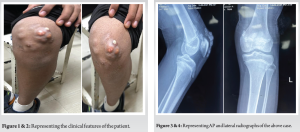

A 12-year-old boy presented to us with chronic nodular swelling in the left knee for the last 2 years. Two years back the boy noticed a single nodular swelling on the anterior aspect of the knee which gradually progressed to multiple swellings on the anterior aspect of knee. Swelling was associated with mild intensity, dull aching, and non-radiating pain over the anterior aspect of knee which progressed to moderate intensity over period of time. Skin was intact initially and when the boy presented to us there was a hard nodular mass over the ulcerated skin. However, there was no restriction of range of motion or any hindrance in activities of daily living. Patient had no history of repetitive trauma or metabolic disorders in the family as proposed in the previous theories of tumoral calcinosis. He also does not have any history of any other swellings in the body or familial history of tumors. He has no associated comorbidities. On examination, about seven swellings were found on the anterior aspect of the left knee each of about 2 × 3 cm size, hard consistency, skin over the medial and inferior swellings was normal but the skin over the lateral swellings was erythematous and ulcerated. Swelling was not fixed to any underlying tissues. Swelling was does not have any particular extension as the swelling did not move with ROM of knee. ROM was however normal. However patellar crepitus was found on examination. No evidence of any other swelling in the body. Distal neurovascular examination was within normal limits (Fig. 1 and 2).

AP and lateral radiographs show cobblestone appearing calcific mass extending from superior aspect of patella extending to the inferior aspect along the pre-patellar region. Intra-articular calcific mass was also found on the radiograph with connection the major mass. Computer Tomography scan was done which confirmed the tumoral calcinosis along the pre-patellar region and a separate intra-articular calcific mass. Complete blood count was found within normal limits, serum calcium, phosphate, alkaline phosphatase, uric acid, and Vitamin D levels were found to be in the normal range when metabolic profile was done (Fig. 3-6).